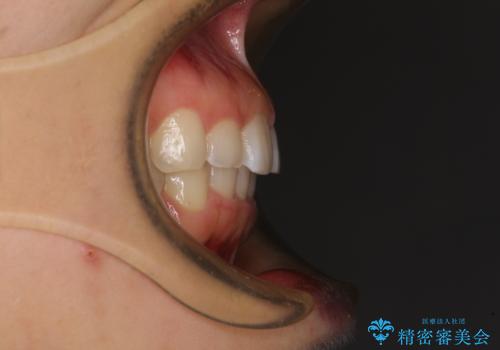

前歯のデコボコと突出感 インビザラインによる矯正治療

- 上下前歯のデコボコと、上顎前歯の突出感を気にして来院された患者様です。

インビザラインによる上下歯列の側方拡大と後方移動、IPR(歯と歯の間を削る)にるスペースの獲得により歯列を整えることとしました。

毎日22時間以上しっかりとマウスピースを装着していただいたので、スムーズに治療が進みました。歯と歯の間を削ることでうまくスペースコントロールでき、1年強で終えることができました。